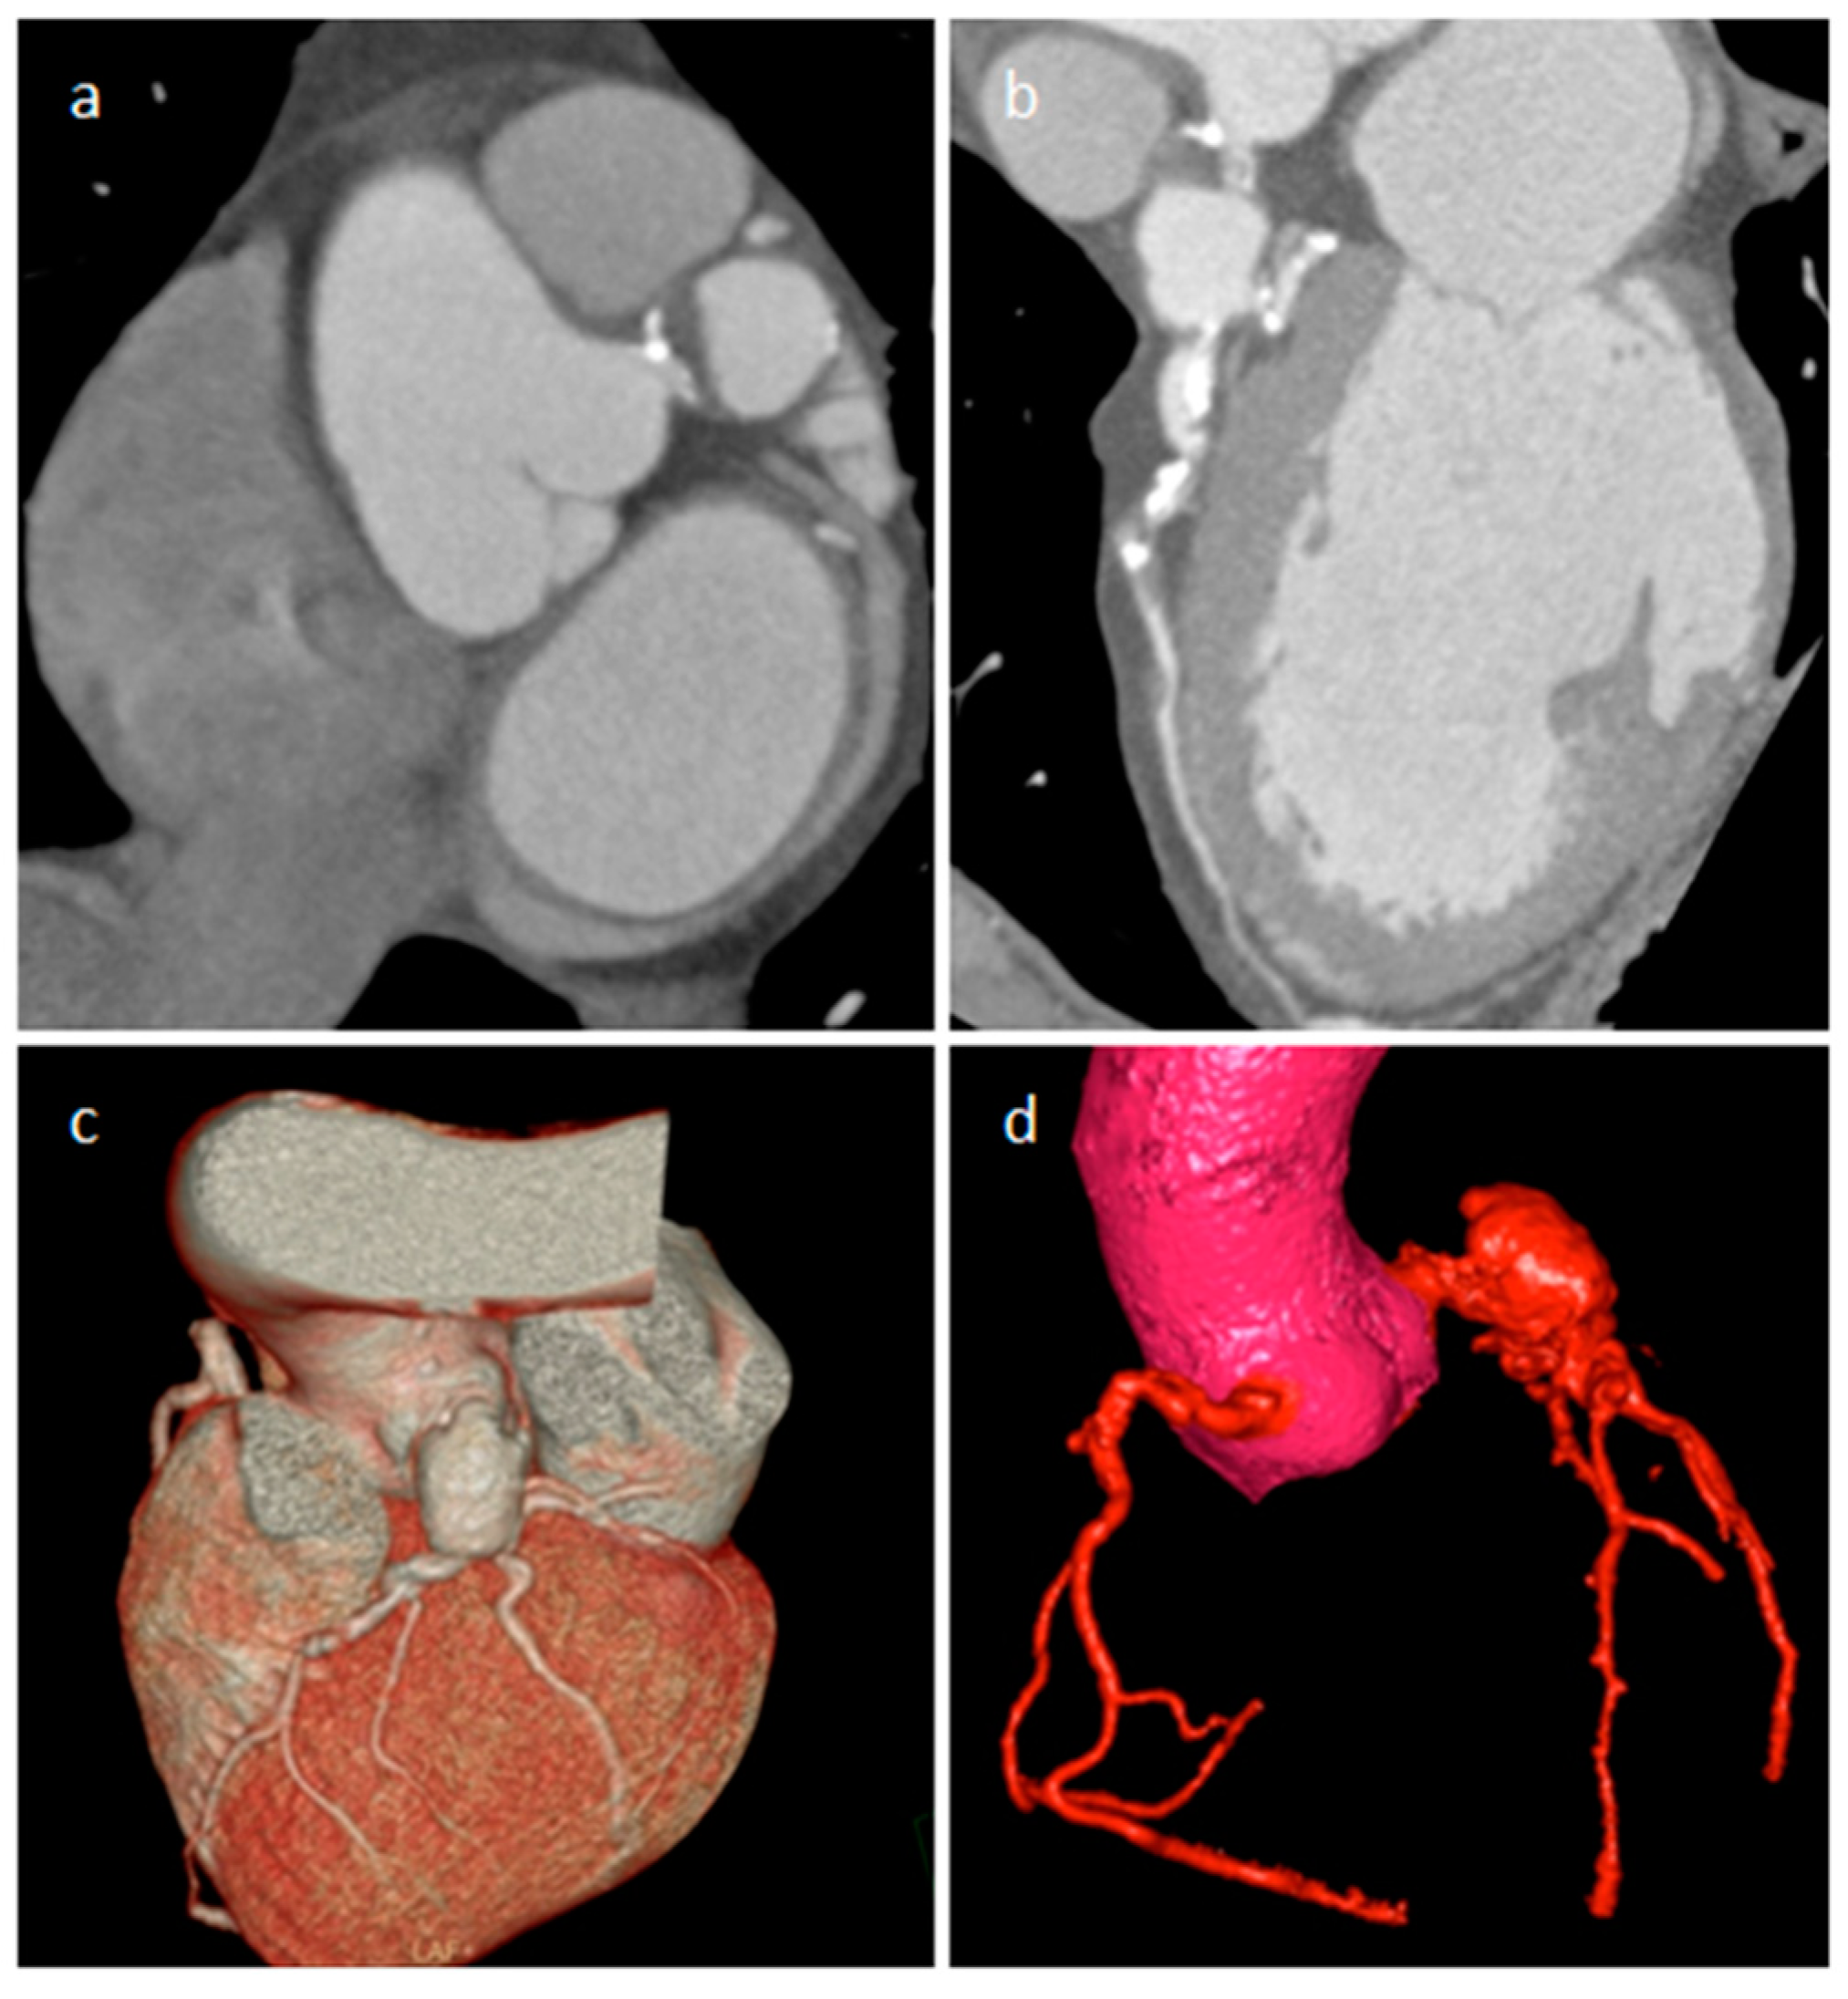

3.5. Coronary Artery Aneurism (CAA)

| Coronary artery aneurisms | Adulthood | AV groove | Asymptomatic | Vascular mass | AV groove mass | Dilatation, thrombus, fistula | Vascular enhancement |